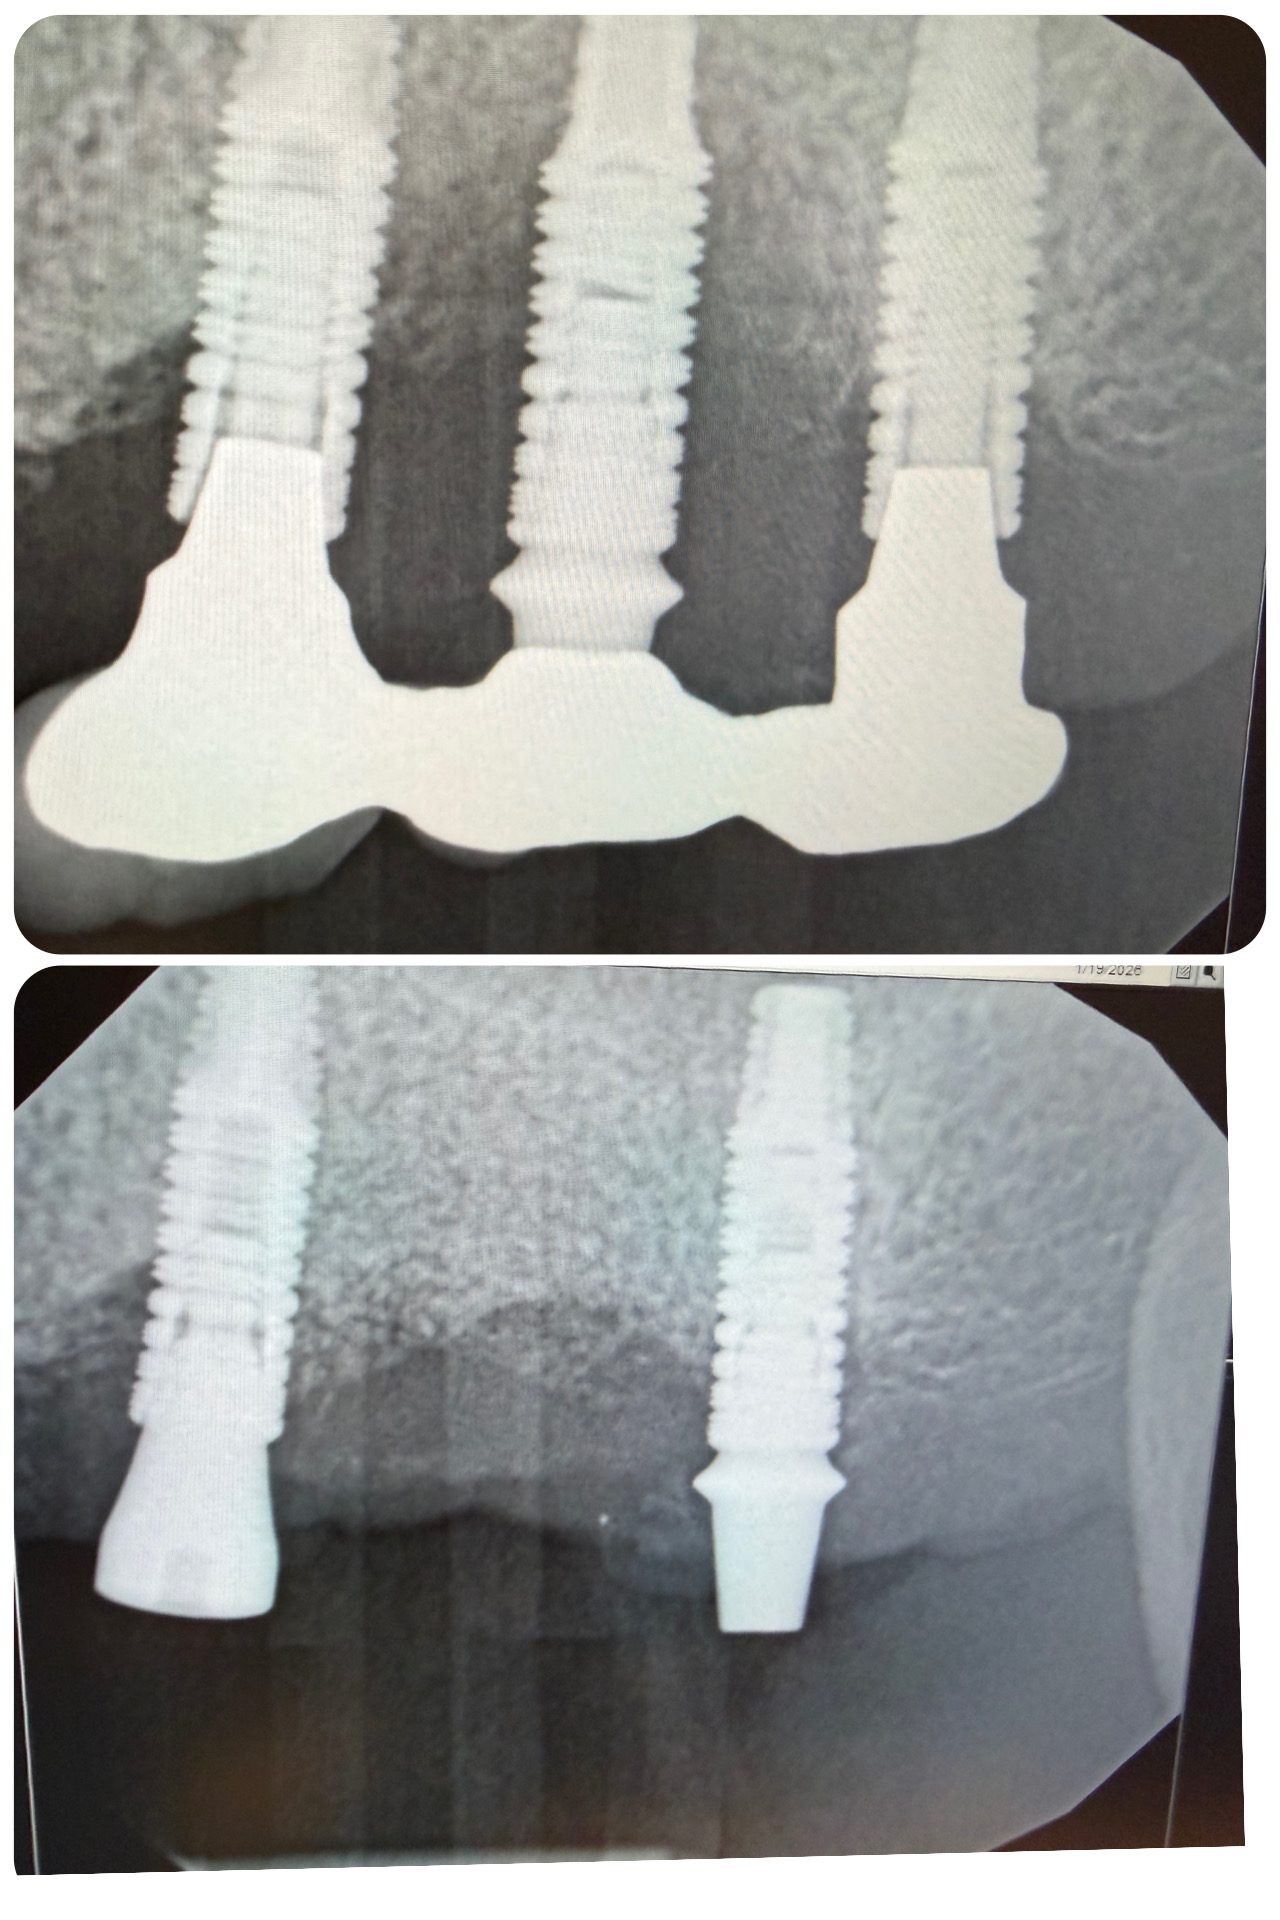

I’d like to briefly share a recent case that highlights an important pattern of peri-implant bone loss increasingly reported in the literature — “Middle Implant Syndrome.”

A recent case series published in Clinical Advances in Periodontics (Prete et al., 2024) describes advanced peri-implant bone loss occurring preferentially around the middle implant of 3-implant splinted fixed dental prostheses.

A patient presented with a splinted 3-unit implant-supported FDP replacing #13–15.

| Radiograph: Severe circumferential bone loss localized to the middle implant (#14) |

- Severe circumferential bone loss around the middle implant (#14)

- Stable bone levels at #13 and #15

- Pattern consistent with the “middle implant” presentation described in the literature